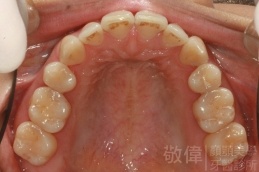

變臉矯正,原來戽斗妹跟大歪臉變成自信正妹

經由本院3D數影X光影像儀分析、與3D齒顎顏矯正技術,再配合口腔顎面正顎專科醫師施以正顎手術治療,雙方共同合作,使患者臉部外觀有很好的改善,大歪變小歪,產生了天南地北的大改變,她的人生也整個變得不一樣。

因為矯正與正顎手術的配合,使「戽斗妹」變成了「陽光正妹」,完全的改變了她的人生,在面對各種場合、與人交際都散發出自信微笑。所以,奉勸家長,如果小朋友有臉顎畸型的問題,應該考慮配合做這種簡單、安全、有效的正顎手術。